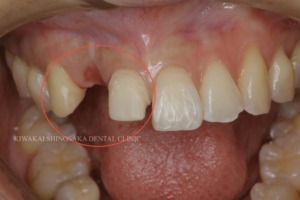

こちらの患者さまは、転倒時に前歯を強打したことで右上2の歯が折れてしまったため、貴和会新大阪歯科診療所へ来院されました。

担当医からは、インプラント1本を欠損部に埋入する治療法か、主訴である右上2の両隣の歯を削り、その上からセラミック素材の被せ物(ジルコニアブリッジ)を装着するといった 2つのプランを患者さまへご提案いたしました。

また詳しく診査・診断を行ったところ、折れてしまった箇所の歯肉が退縮していたため、どちらかの治療を選択されたとしても、歯肉の厚みを増やす【結合組織移植術(CTG)】を行う必要があることもお伝えいたしました。

患者さまとご相談の結果、両隣の健康な歯を削ることにはなりますが、仮歯を装着することができるため、治療期間中の見た目に支障がないことや、インプラント治療と比べて短い期間で治療を終えられることから、セラミックを用いた修復治療(ジルコニアブリッジ)にて進めていく事になりました。

まず右上1と3の歯を削った後、作製した右上1・2・3の連なった仮歯を装着しました。